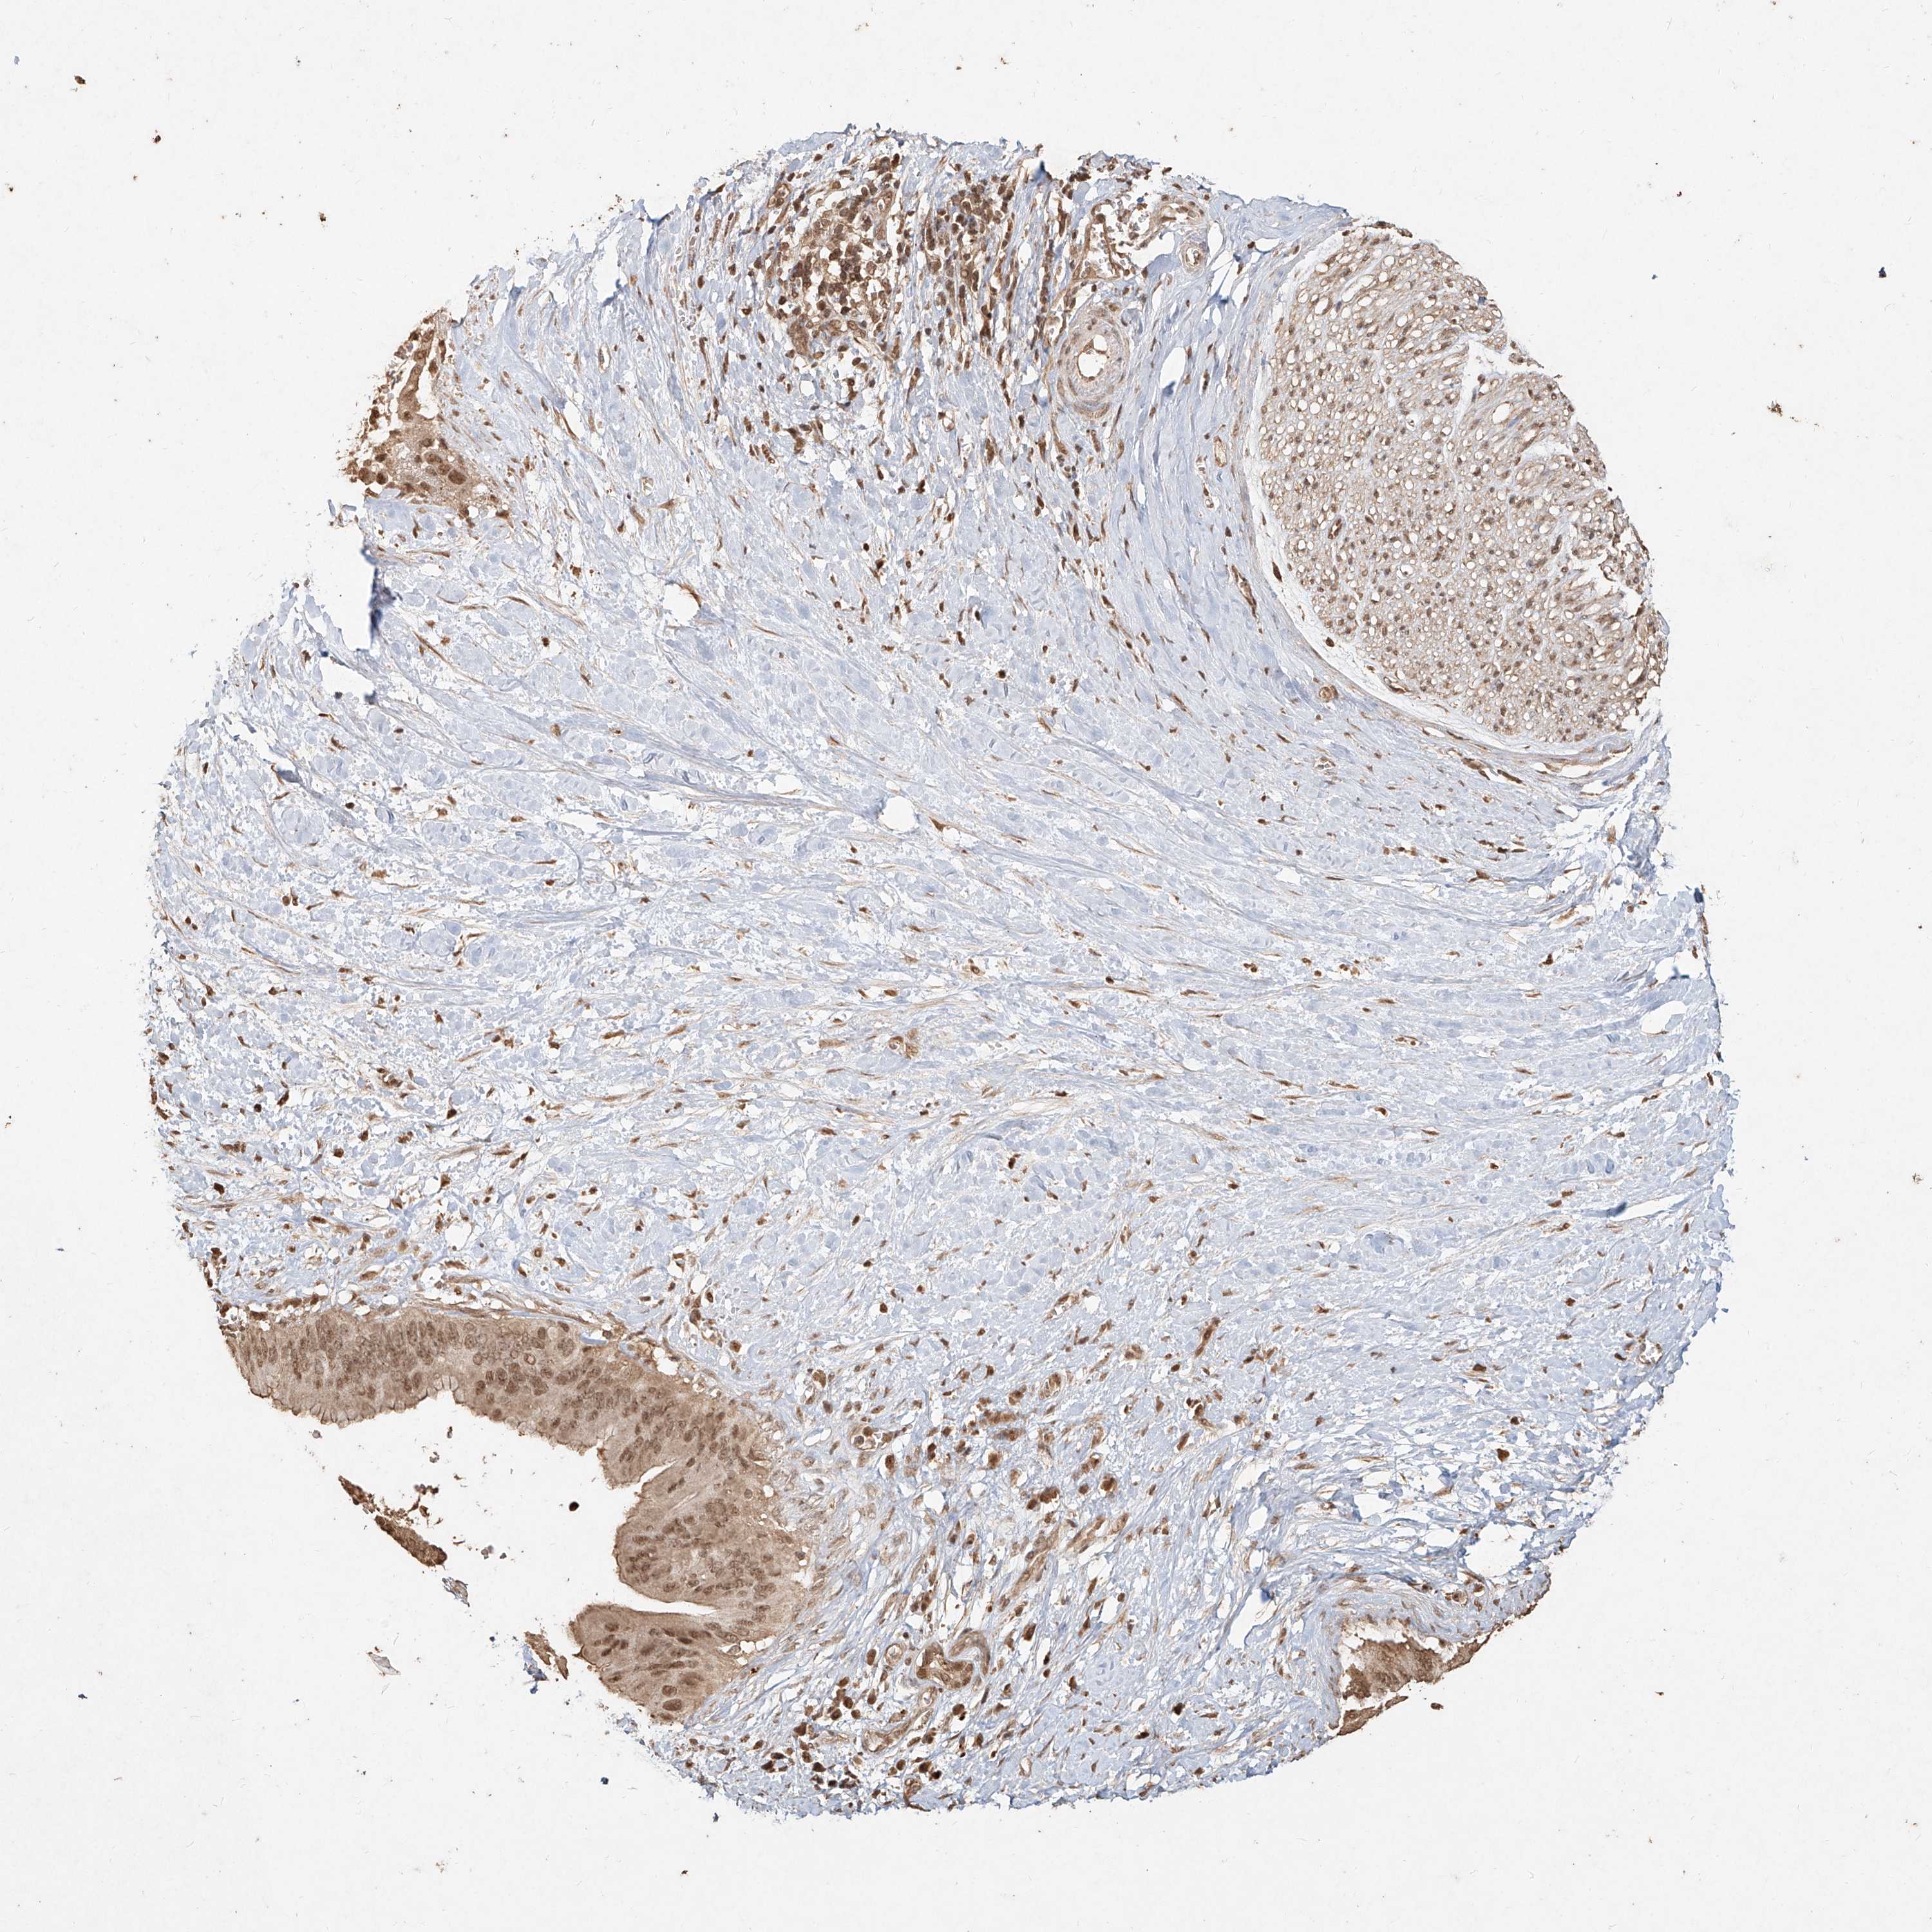

PANCREATIC CANCER - Protein expressioni

A mouse-over function shows sample information and annotation data. Click on an image to view it in a full screen mode. Samples can be filtered based on level of antibody staining by selecting one or several of the following categories: high, medium, low and not detected. The assay and annotation is described here.

Note that samples used for immunohistochemistry by the Human Protein Atlas do not correspond to samples in the TCGA dataset.

Antibody stainingi

Antibody staining in the annotated cell types in the current human tissue is reported as not detected, low, medium, or high, based on conventional immunohistochemistry profiling in selected tissues. This score is based on the combination of the staining intensity and fraction of stained cells.

Each image is clickable and will lead to virtual microscopy that enables deeper exploration of all samples and also displays staining intensity scores, fraction scores and subcellular localization as well as patient and tissue information for each sample.

Antibody HPA028869

Antibody CAB033212

Antibody CAB033515

Staining

High

Medium

Low

Not detected

Intensity

Strong

Moderate

Weak

Negative

Quantity

>75%

75%-25%

<25%

None

Location

Nuclear

Cytoplasmic/membranous

Cytoplasmic/membranous,nuclear

Adenocarcinoma, NOS